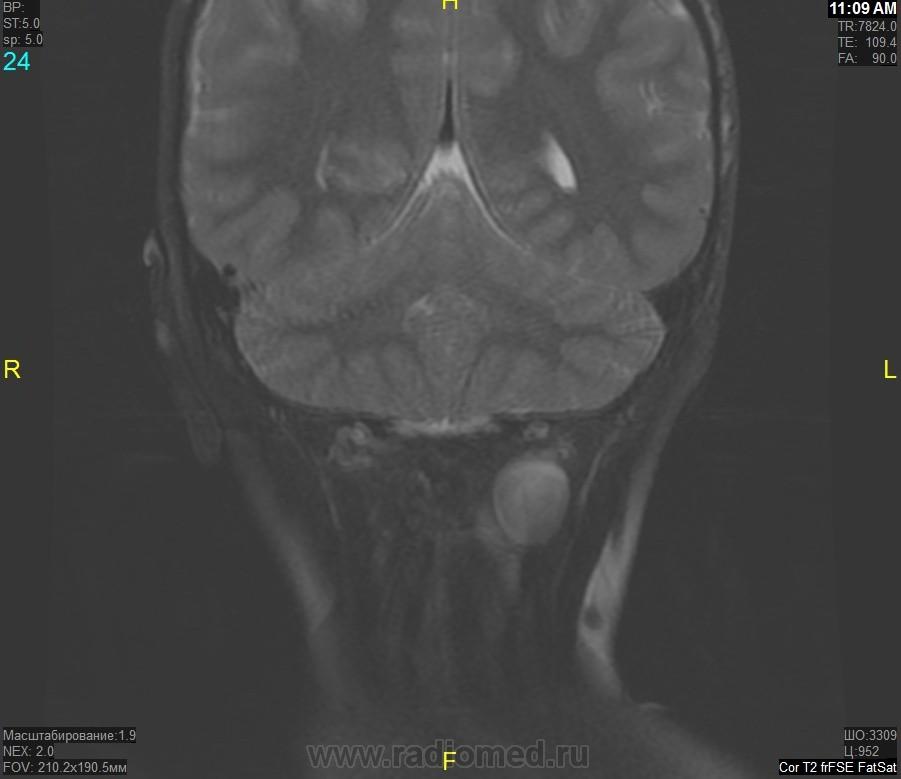

Уважаемые коллеги! Прошу консультативной помощи. Про пациента известно: девочка (7 лет), в анамнезе 2,5 года назад травма головы. Не диагностировалась. Периодически жалобы на болезненность при пальпации затылочной области(((((

Напоминает сосудистую структуру.Может, какая-нибудь лимфангиома?Видела на передней поверхности шеи, на задней - нет.

как будто связь с ликвором имеется.  Дополнил бы венографией, и FatSat"ом ну и контрастом, конечно.

Сегодня в ходе разговора с мамой девочки, выяснилось, что и у мамы есть подобное "образование". С ее слов, несколько лет назад ей делали пункцию для исключения онкологии. Результат пункции: содержится нервная ткань и лимфоциты ( опять же никаких документов я не видела). То есть можно говорить о наследственном характере.

Нейрофиброма вполне может быть. Плексиформная. Проверить на нейрофиброматоз. Я видел такой же структуры и локализации. Пятен на коже нет? Вообще на теле? И нет ли чего похожего в позадиглоточном пространстве?

есть похожее образование в позадиглоточном пространстве)

многоузловое образование  исходящее из задней части предпозвоночного пространства с переходом на подкожную жировую клетчатку головы!шваннома ,нейрофиброма и их злокачественные аналоги